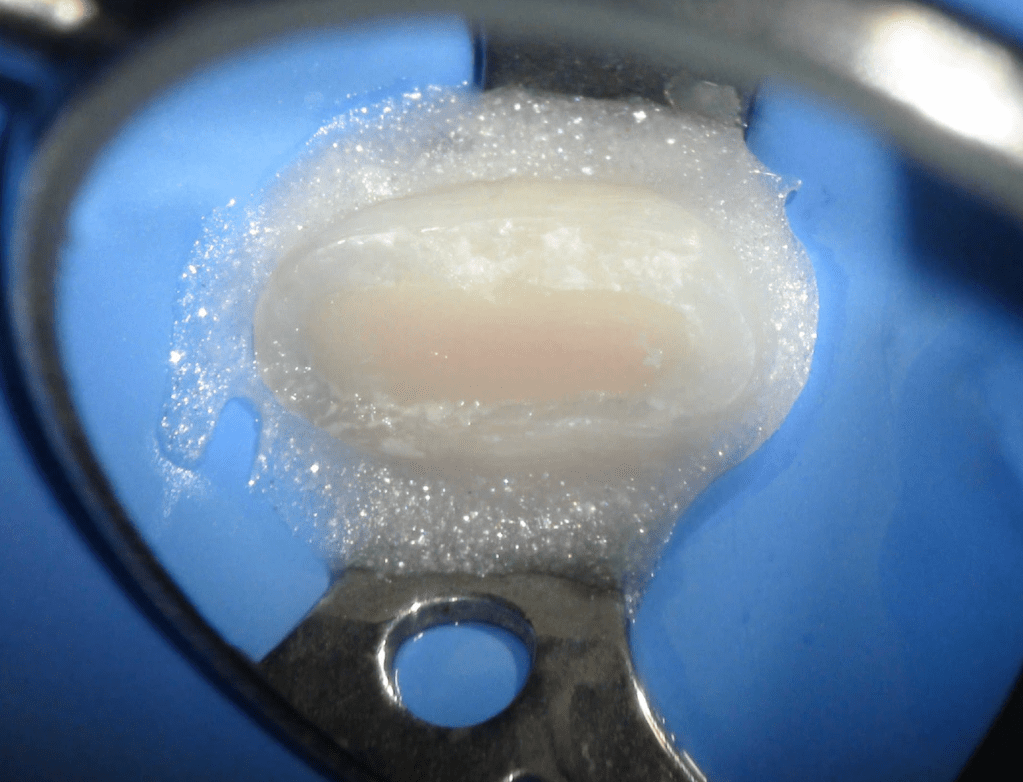

Reco palatina